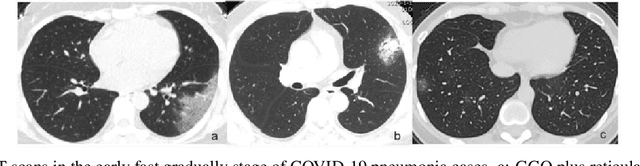

Abstract:The new coronavirus disease (COVID-19) has been declared a pandemic since March 2020 by the World Health Organization. It consists of an emerging viral infection with respiratory tropism that could develop atypical pneumonia. Experts emphasize the importance of early detection of those who have the COVID-19 virus. In this way, patients will be isolated from other people and the spread of the virus can be prevented. For this reason, it has become an area of interest to develop early diagnosis and detection methods to ensure a rapid treatment process and prevent the virus from spreading. Since the standard testing system is time-consuming and not available for everyone, alternative early-screening techniques have become an urgent need. In this study, the approaches used in the detection of COVID-19 based on deep learning (DL) algorithms, which have been popular in recent years, have been comprehensively discussed. The advantages and disadvantages of different approaches used in literature are examined in detail. The Computed Tomography of the chest and X-ray images give a rich representation of the patient's lung that is less time-consuming and allows an efficient viral pneumonia detection using the DL algorithms. The first step is the pre-processing of these images to remove noise. Next, deep features are extracted using multiple types of deep models (pre-trained models, generative models, generic neural networks, etc). Finally, the classification is performed using the obtained features to decide whether the patient is infected by coronavirus or it is another lung disease. In this study, we also give a brief review of the latest applications of cough analysis to early screen the COVID-19, and human mobility estimation to limit its spread.

Abstract:The new coronavirus 2019, also known as COVID19, is a very serious epidemic that has killed thousands or even millions of people since December 2019. It was defined as a pandemic by the world health organization in March 2020. It is stated that this virus is usually transmitted by droplets caused by sneezing or coughing, or by touching infected surfaces. The presence of the virus is detected by real-time reverse transcriptase polymerase chain reaction (rRT-PCR) tests with the help of a swab taken from the nose or throat. In addition, X-ray and CT imaging methods are also used to support this method. Since it is known that the accuracy sensitivity in rRT-PCR test is low, auxiliary diagnostic methods have a very important place. Computer-aided diagnosis and detection systems are developed especially with the help of X-ray and CT images. Studies on the detection of COVID19 in the literature are increasing day by day. In this study, the effect of different batch size (BH=3, 10, 20, 30, 40, and 50) parameter values on their performance in detecting COVID19 and other classes was investigated using data belonging to 4 different (Viral Pneumonia, COVID19, Normal, Bacterial Pneumonia) classes. The study was carried out using a pre-trained ResNet50 convolutional neural network. According to the obtained results, they performed closely on the training and test data. However, it was observed that the steady state in the test data was delayed as the batch size value increased. The highest COVID19 detection was 95.17% for BH = 3, while the overall accuracy value was 97.97% with BH = 20. According to the findings, it can be said that the batch size value does not affect the overall performance significantly, but the increase in the batch size value delays obtaining stable results.